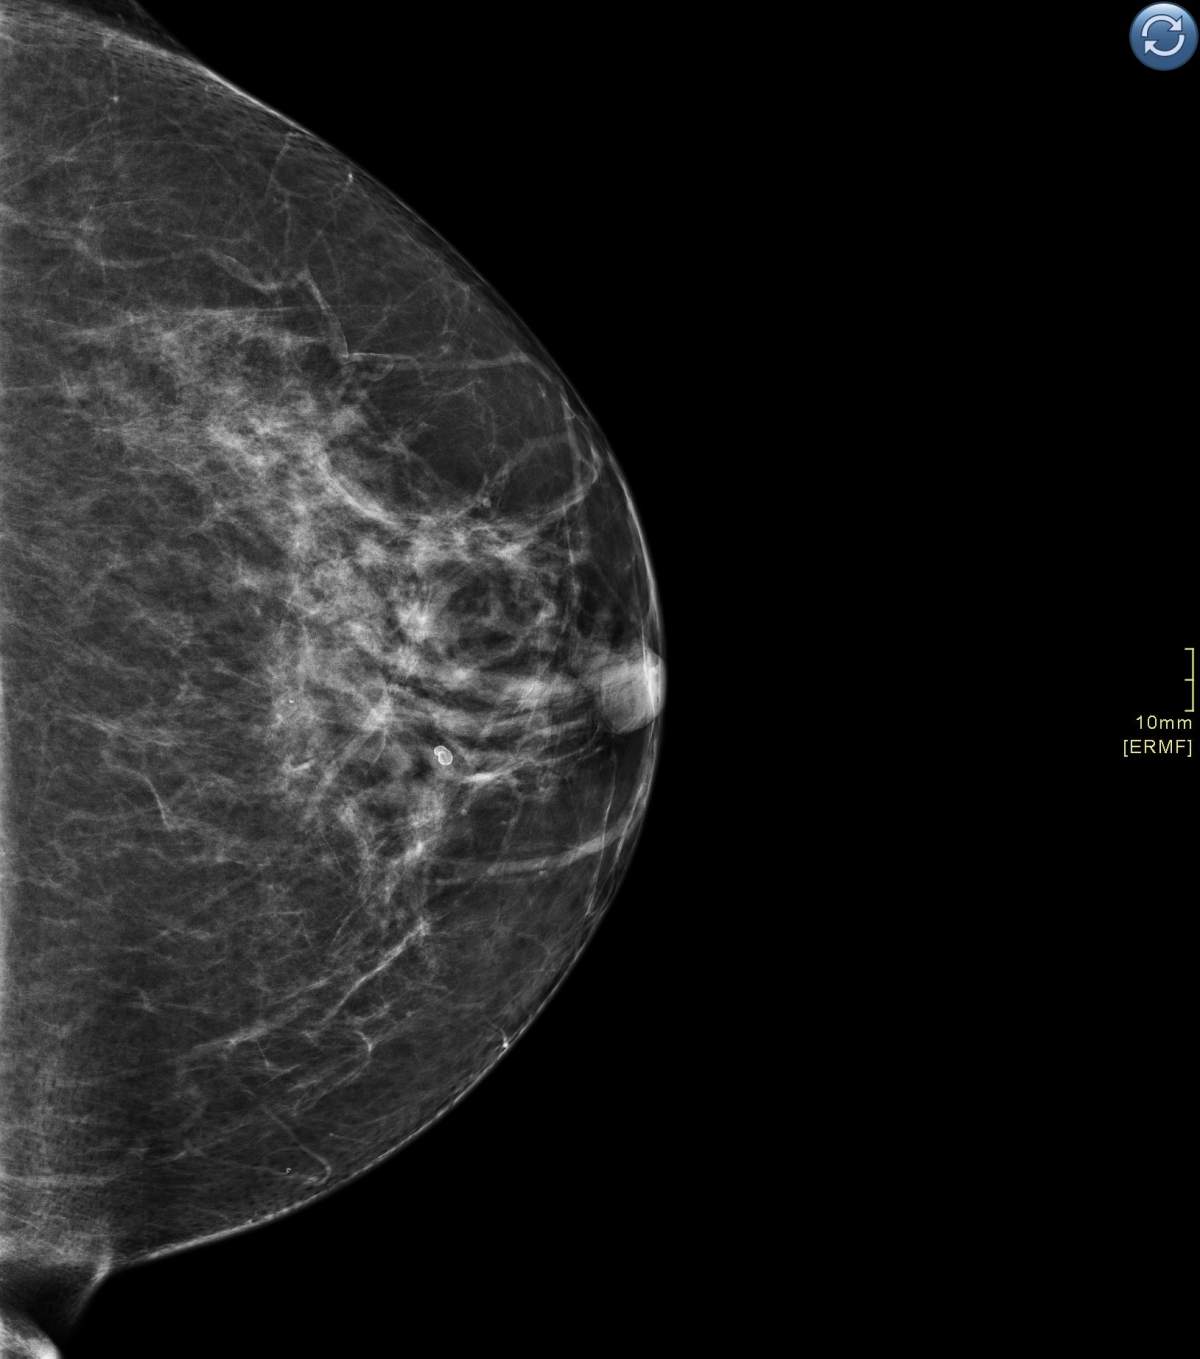

The imaging is called digital breast tomosynthesis and is a type of 3D imaging. Researchers out of Lawson Research Institute want to learn whether it is better at finding abnormalities than the conventional digital 2D mammogram.

“One of the limitations we face with [how we currently do] mammograms is overlapping breast tissue,” said Dr. Anat Kornecki, Lawson scientist and radiologist at St. Joseph’s.

“When we only have two-dimensional views, it’s very difficult to separate a lesion from overlapping breast tissue, especially if the patient has dense breast tissue, which affects about 40 per cent of patients.”

This is different from a conventional 2D mammogram, in which two X-ray images are taken of the breast: one from top to bottom, the other from side to side at an angle.